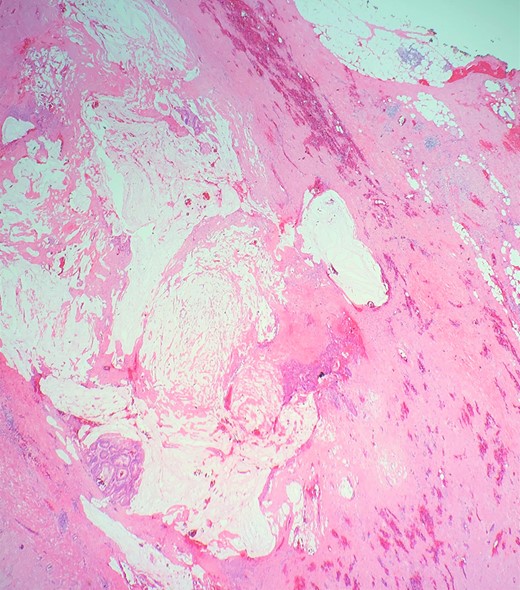

Definitive histological examination showed perforated appendix involved by moderately differentiated mucinous adenocarcinoma (Fig. 5), arising in the background of diffuse tubulovillous adenoma with extensive high-grade dysplasia and showed cellular mucin within the periappendiceal soft tissue (Figs 6 and 7). Proximal cecal mucosal margin and mesenteric margin uninvolved by carcinoma and four periappendicular lymph node was negative for metastatic carcinoma and pathological stage aided for pT4a, pN0. The post-operative course was uneventful. The tumor was staged as T4N0M0 (Modified Astler Coller B3). Patient was referred for oncology and for multidrug adjuvant chemotherapy of 5-fluorouracil, lecovorin and oxalipatin (FOLFOX) was given. Patient was asymptomatic during the 2 weeks, 3 months and 6 months follow up.

This demonstrates mucinous tumor with pushing invasion through the appendiceal wall.